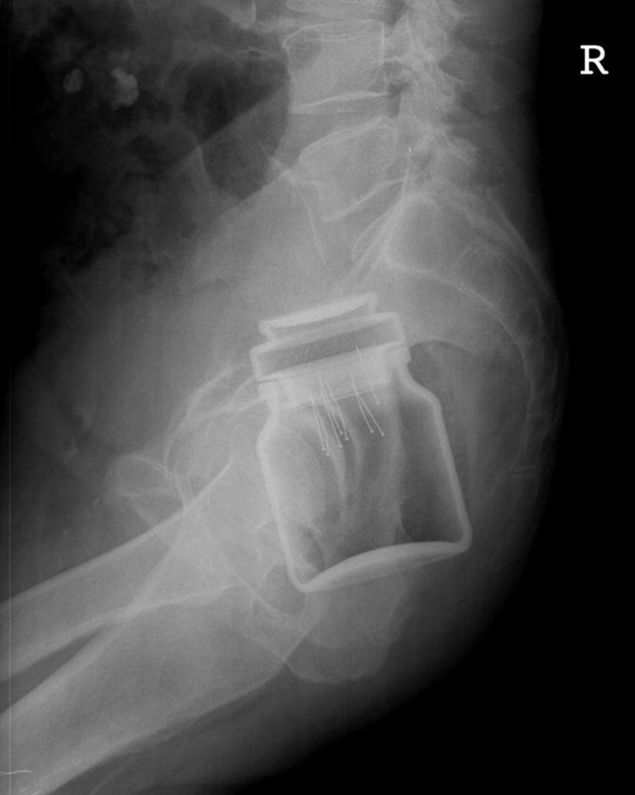

Nu mica le-a fost surpriza cadrelor medicale atunci cand un alt barbat a ajuns la Urgente cu un borcan de cafea in zona rectala. Inainte sa experimenteze cu borcanul, individul, din motive nestiute, a infipt cateva cuie in capacul borcanului.